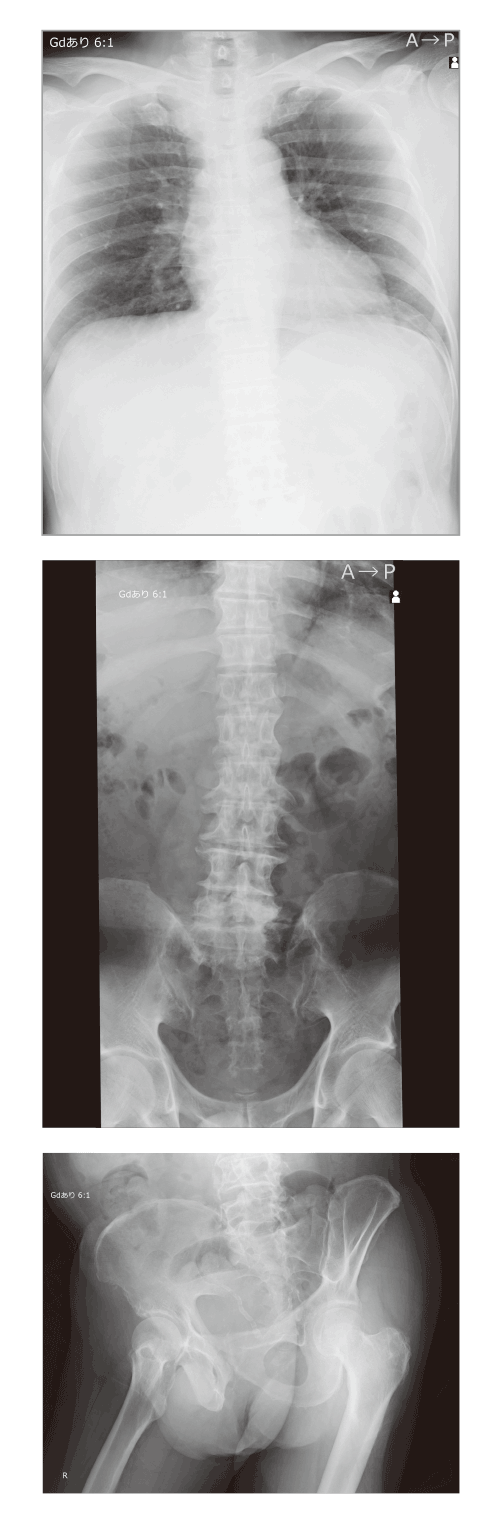

散乱線補正処理「インテリジェントグリッド」

散乱線補正処理「インテリジェントグリッド」との併用により、使用シーンはさらに拡大。ポータブル撮影などグリッドを使用しにくい撮影でも高品位な画像を提供します。

<対象部位>

頭部正面/頸椎/肩関節/胸部正面/胸部側面/胸椎/腰椎/胸腰椎/腹部正面/骨盤/股関節/大腿骨/小児胸部正面/鎖骨正面/膝関節正面/膝関節側面/膝関節斜位